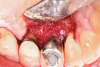

A surgical approach was planned that included implantoplasty and guided bone regeneration. After local anesthesia was administered, full-thickness flaps were elevated using an envelope flap on the buccal aspect and a triangular design on the palate to expose the defects. Removal of granulomatous tissue from the area enabled visualization of a narrow circumferential lesion on the facial (Figure 3) and a one- to two-wall combination defect on the palatal (Figure 4). The surface was initially treated with a 50% solution of citric acid for 30 seconds followed by thorough rinsing with sterile saline. This was followed by implantoplasty using a 30-fluted finishing bur of surgical length. Because the implant was very narrow, achieving a matte-like surface was not possible; thus, the goal was to reduce the threads and lightly remove the implant's outer surface to expose fresh titanium (Figure 5 and Figure 6). The modified surface was treated again with citric acid and rinsed with sterile saline.

Fig 3. A narrow three-wall infrabony defect was visualized on the facial of the implant.

Figure 3